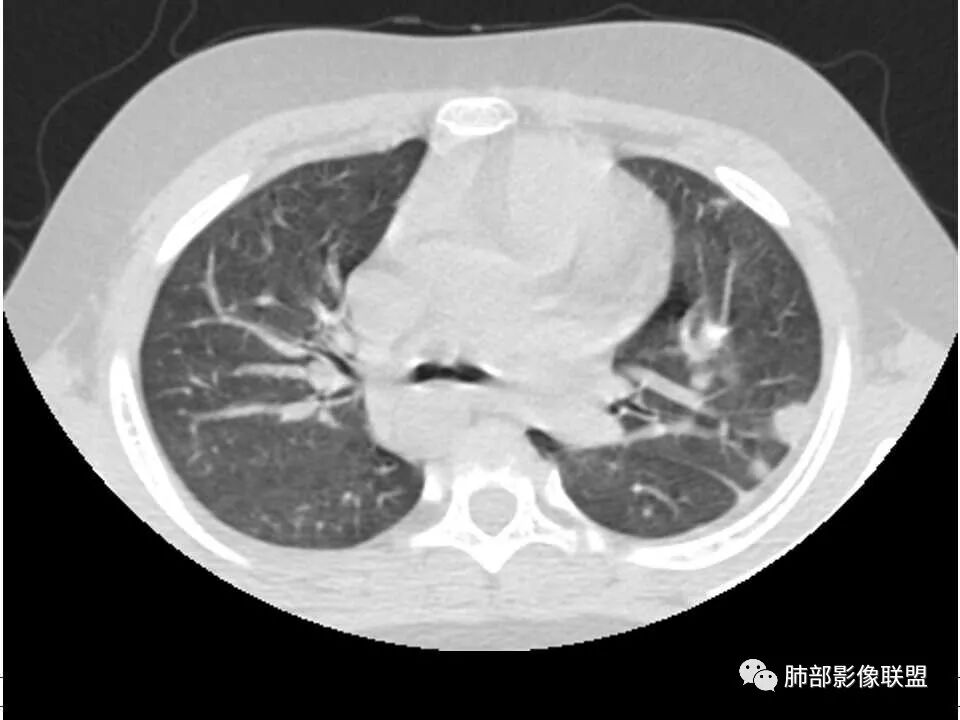

患者儿童,因右下肢疼痛伴肿胀14天就诊。病程中有发热及伴随症状。膝关节MRI提示右侧膝关节及右髌骨髁异常信号影,右膝髌上囊及关节腔内少量积液。胸部CT:双肺胸膜下多发结节影,部分结节空洞形成,且结节周围可见血管集束征。综合考虑血源性脓毒性肺栓塞、坏死性肺炎。右侧骨髓炎、血播性金葡菌肺炎,鉴别其他特殊感染及血管炎。

胸部ct:双肺多发空洞,结节,外带下叶为主,空洞内外光滑,有血管滋养征,综合病史及影像考虑脓毒性肺栓塞,结合病史,金葡可能性大。

小儿,急性起病,下肢疼痛,mr提示骨髓水肿,临床化验炎性指标高,考虑金葡菌骨髓炎,双肺多发结节,以血管支气管束及胸膜下分布为主,部分结节近端与血管相连,部分结节可见空腔,内壁光整,部分囊腔有张力,考虑骨髓炎并肺内血播感染,金葡?

2.双肺多发片影,随机分布,多空洞或囊腔,胸膜下多楔形影,气道未见受累等等符合脓毒血症影像学表现,尤其是金葡。

1. 多发胸膜下外周结节、< 3 cm 的楔形影和滋养血管征 CT 表现;

4.经恰当的抗生素治疗,肺部浸润影吸收。滋养血管征为一支血管影连接肺部周边病灶,在 2/3 以上患者出现,可作为高度提示 SPE 的征象。